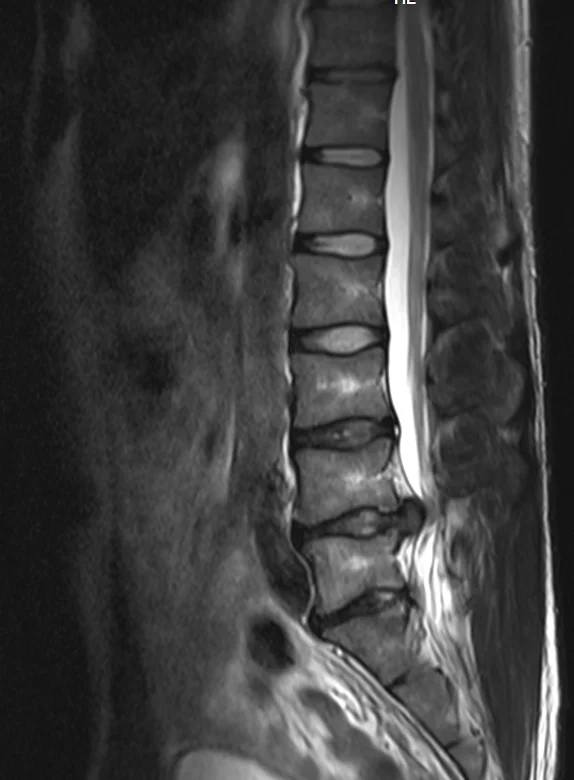

Eilisen tilanne magneetissa. Oikeasssa kankussa/lonkan seudulla ollut keväästä asti särkyä ulkokierrossa ja selällään on ollut vaikea maata. Tai oikeastaan mahdotonta niin että kankku ei olisi pienessä jännityksessä. Välillä kipu säteilee nilkkaan. Kuitenkin tuon kanssa on pystynyt elämään ja liikkumaankin kohtuullisesti.

Olen ollut sitä mieltä että kipu on lihasperäistä (tulehduksesta esim. ja liiasta autossa ja tuolilla istumisesta toimistotyöstä johtuen) ja olen sitä mieltä edelleen. Oikeastihan tuo pullistuma (joka on vasemmalla puolella) on kuvissa pahentunut, mutta vasemmalle puolelle ei kipua ole käytännössä ole ollut enää kevään jälkeen. Yksi selkä, yksi elämä. Kuvissa lokakuu 2012, maaliskuu 2013 ja joulukuu 2013.

Lekurille oli tunnin aika ja tuossa kerkesi jo oikeasti tutkia melko hyvin, lääkärillä oli aikaa kuunnella ja selittää teoriaa melko ymmärrettävästi. Tosin laskukin oli sellaiset 250€. Tuo oma pullistuma on jäätävän kokoinen kun sitä katsoo päältäpäin otetusta kuvasta. Siltikin on mielenkiintoista miten vasemmallapuolella ei ole oireita, vaikka pullistuma on siellä ja painaa selvästi hermoa. Oli myös lohdullista kuulla että jos tuo leikataan, ei kauheasti tartte ottaa stressiä siitä että pullistuma uusiutuu. Nimittäin ei ole enää sen jälkeen mitään mitä pullistua ulos. Kuvissa näkee miten ylemmässä välissä on ollut tuo annulusvaurio 9kk ajan, eikä sekään ole siitä mihinkään korjaantunut.